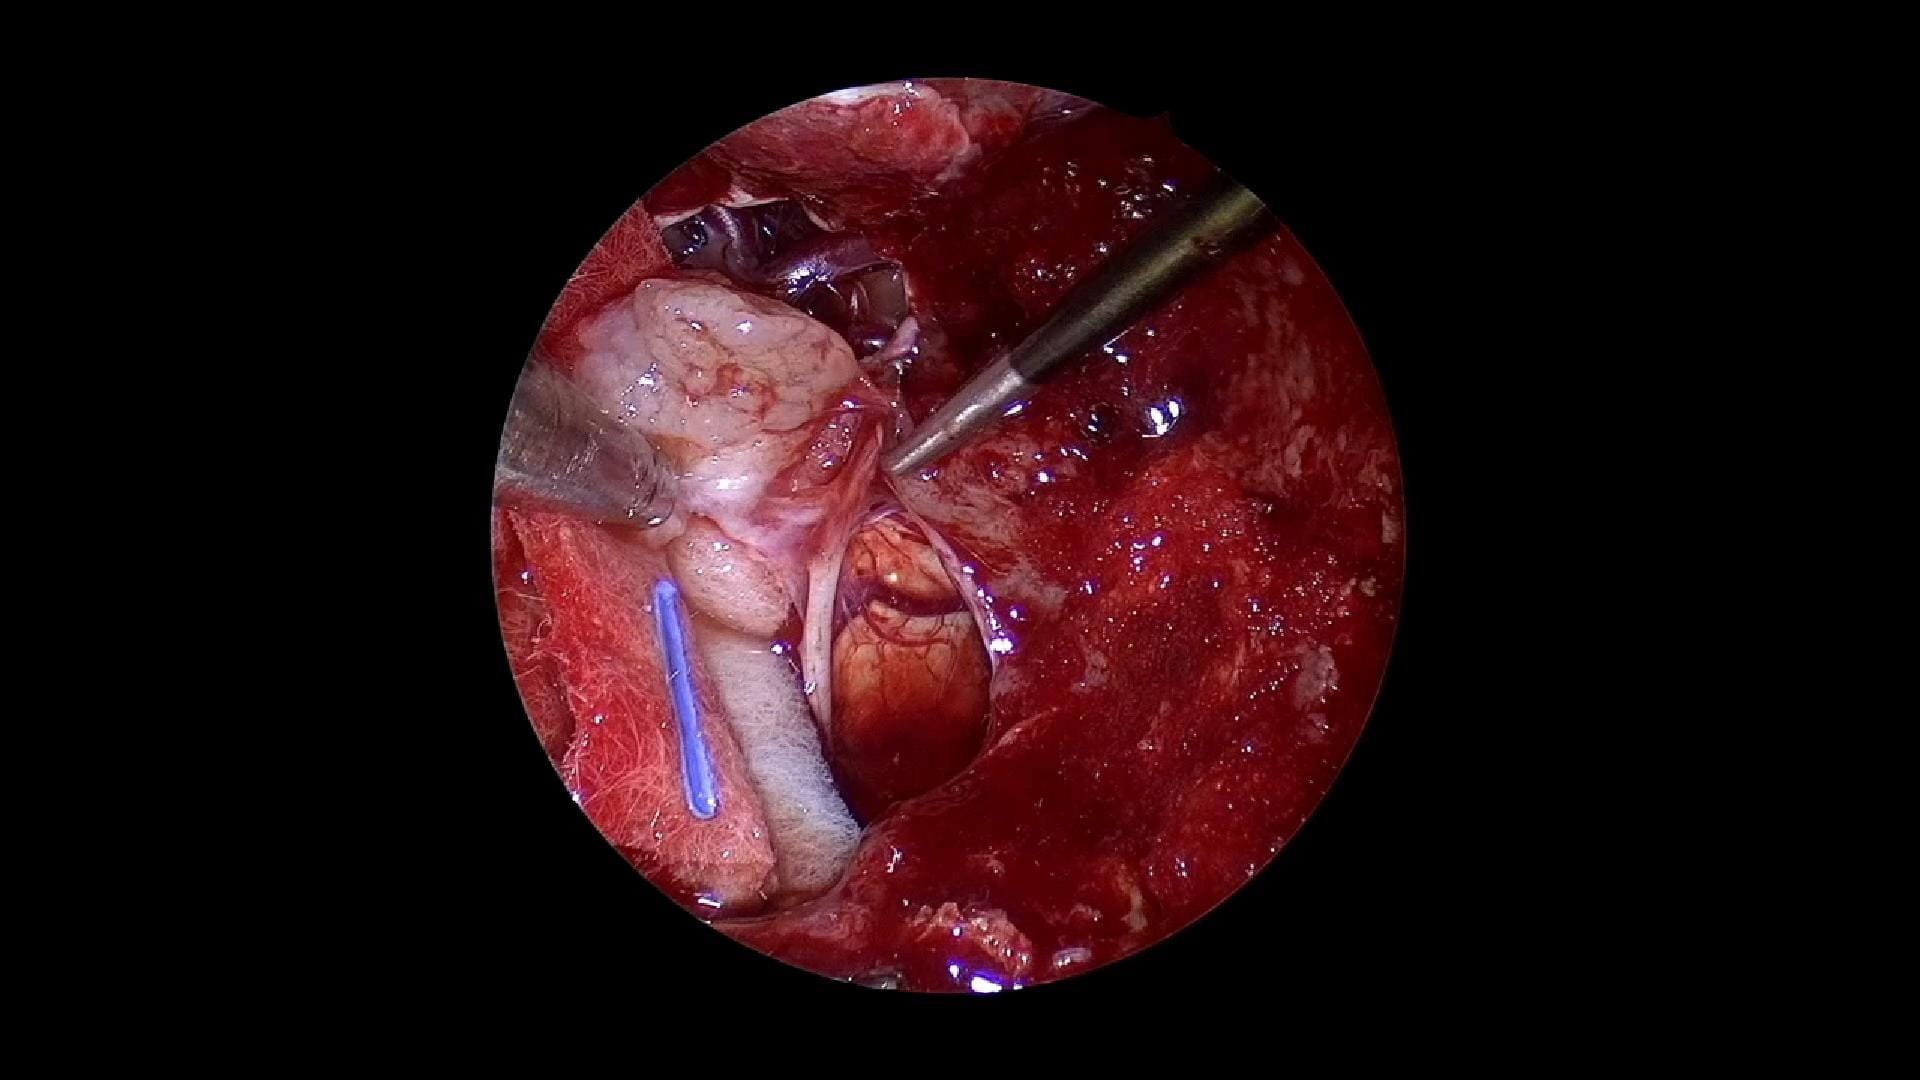

Durante la resección, se identifican y disecan cuidadosamente estructuras críticas como la arteria basilar, los vasos perforantes, y el nervio craneal VI, infiltrado por el tumor y sacrificado por disfunción previa y ausencia de respuesta eléctrica.

Se logra una resección amplia con descompresión del tronco cerebral, aunque persisten restos tumorales en regiones profundas como Meckel, seno cavernoso y ápex petroso.

Se exponen estructuras clave como el ganglio de Gasser, nervios craneales V, IV y III, y el conducto auditivo interno. El cordoma es resecado de forma meticulosa, incluso medial y caudal al nervio trigémino, hasta alcanzar la duramadre de fosa posterior.

La cirugía finaliza con una visualización completa del tronco encefálico y márgenes negativos confirmados por anatomía patológica. La paciente tolera bien la intervención y posteriormente se somete a cirugía correctora del estrabismo.